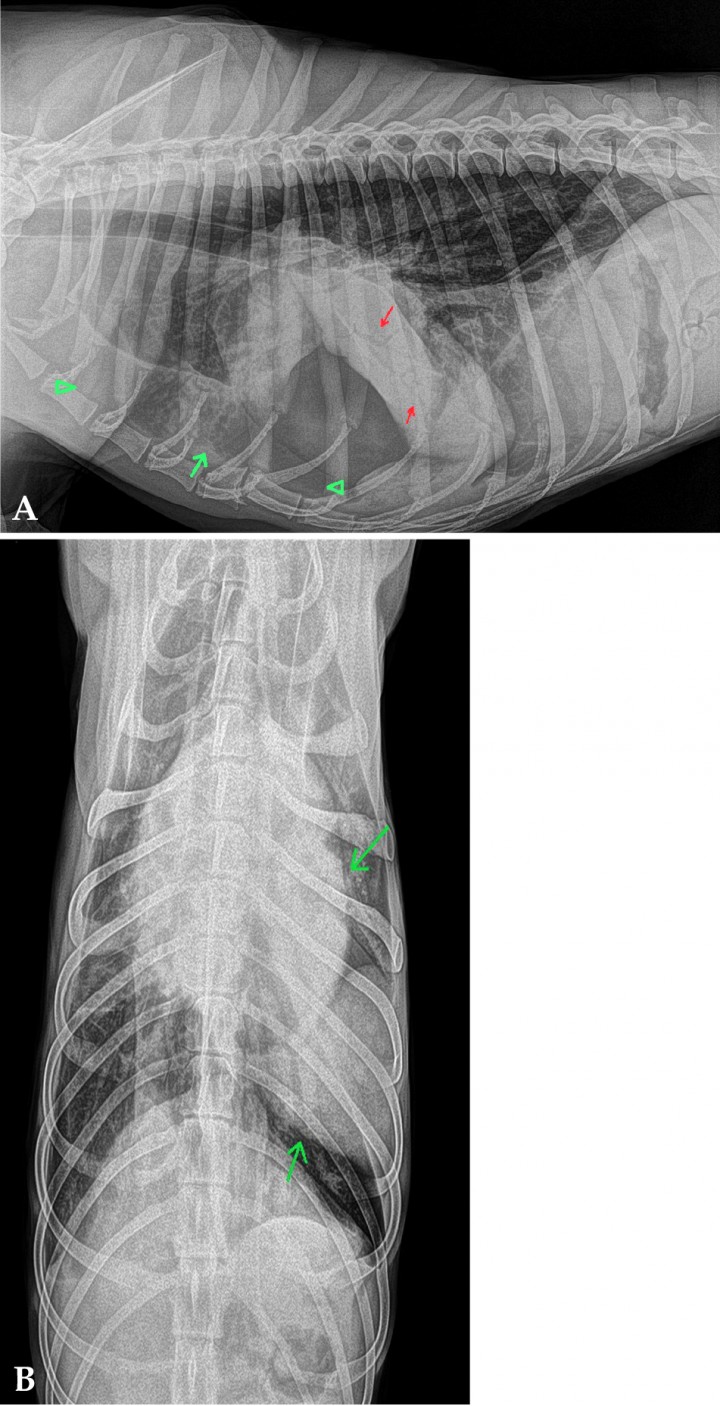

La prueba definitiva de diagnóstico fue la tomografía computarizada (TC). En el estudio se observó la porción caudal del lóbulo craneal izquierdo torsionada sobre sí misma a nivel del hilio. El lóbulo aparecía consolidado y aumentado de volumen, presentando una dirección caudodorsal anormal. El bronquio de este lóbulo estaba interrumpido a nivel del hilio (Fig. 4).

<p>(<strong>A</strong>) Corte transversal en ventana tejido blando. (<strong>B</strong>) Corte dorsal en ventana tejido blando. Se observa la porción caudal del lóbulo craneal izquierdo torsionada a nivel del hilio. El lóbulo aparece consolidado, aumentado de volumen y mal posicionado. El bronquio aparece interrumpido a nivel del hilio (flechas verdes).</p>

(A) Corte transversal en ventana tejido blando. (B) Corte dorsal en ventana tejido blando. Se observa la porción caudal del lóbulo craneal izquierdo torsionada a nivel del hilio. El lóbulo aparece consolidado, aumentado de volumen y mal posicionado. El bronquio aparece interrumpido a nivel del hilio (flechas verdes).

En el interior de la porción caudal del lóbulo craneal izquierdo se observó un patrón vesicular. Se evidenció un pequeño volumen de neumotórax, más acusado en hemitórax izquierdo, coincidiendo con la posición del drenaje pleural, así como un discreto neumomediastino y enfisema intersticial alrededor de la arteria pulmonar del lóbulo caudal derecho (Fig. 5).